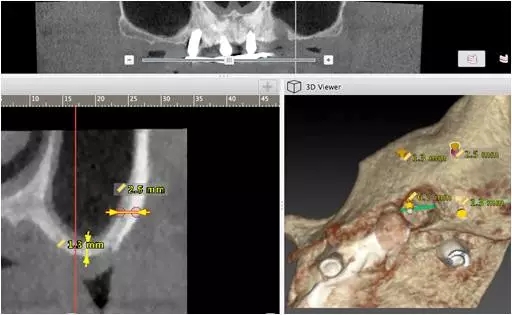

10個(gè)月后出現(xiàn)左上頜咬合痛,X線檢查發(fā)現(xiàn)上頜左側(cè)前磨牙區(qū)傾斜種植體周圍低密度影,臨床檢查種植體松動(dòng),其余種植體骨結(jié)合良好,遂拔除該種植體(圖3-4)。愈合3個(gè)月,CBCT片顯示:25區(qū)種植窩空虛(圖5),愈合不佳,26區(qū)竇底剩余骨高度不足2mm(圖6),其余種植體骨愈合良好,15區(qū)傾斜種植體邊緣骨疑似吸收至第三螺紋(結(jié)合全景片)?;颊咭蠊潭ㄐ迯?fù)。

圖5

圖6